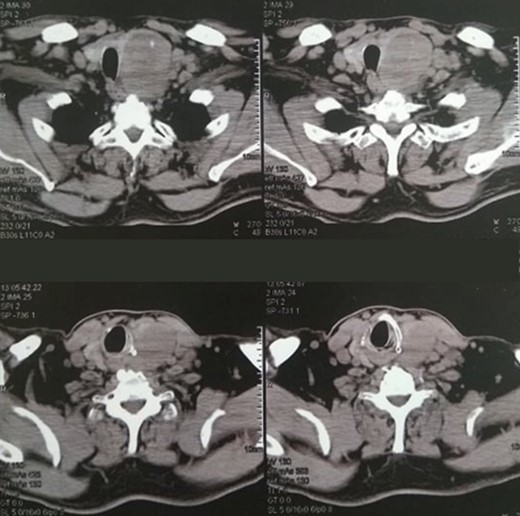

A 58-year-old man, diagnosed with left thyroid lobe carcinoma, was admitted to our department for further treatment. His condition was diagnosed incidentally, upon cardiologic and imaging examination during investigation of shortness of breath and fatigue. Abnormal enlargement of the left thyroid lobe due to a 7-cm node was primarily found in cervical ultrasound, as well as enlargement of multiple left cervical lymph nodes. Further imaging with cervical and thoracic computerized tomography (CT) (Fig. 1) and FNA biopsy indicated a Bethesda System сategory V neoplasia. Preoperative research also included serum calcitonin, to exclude myeloid carcinoma, and lymph node mapping (Fig. 2).

Cervical CT scan, showing a 7-cm node of the left thyroid lobe and concommitent multiple left cervical nodal enlargement.